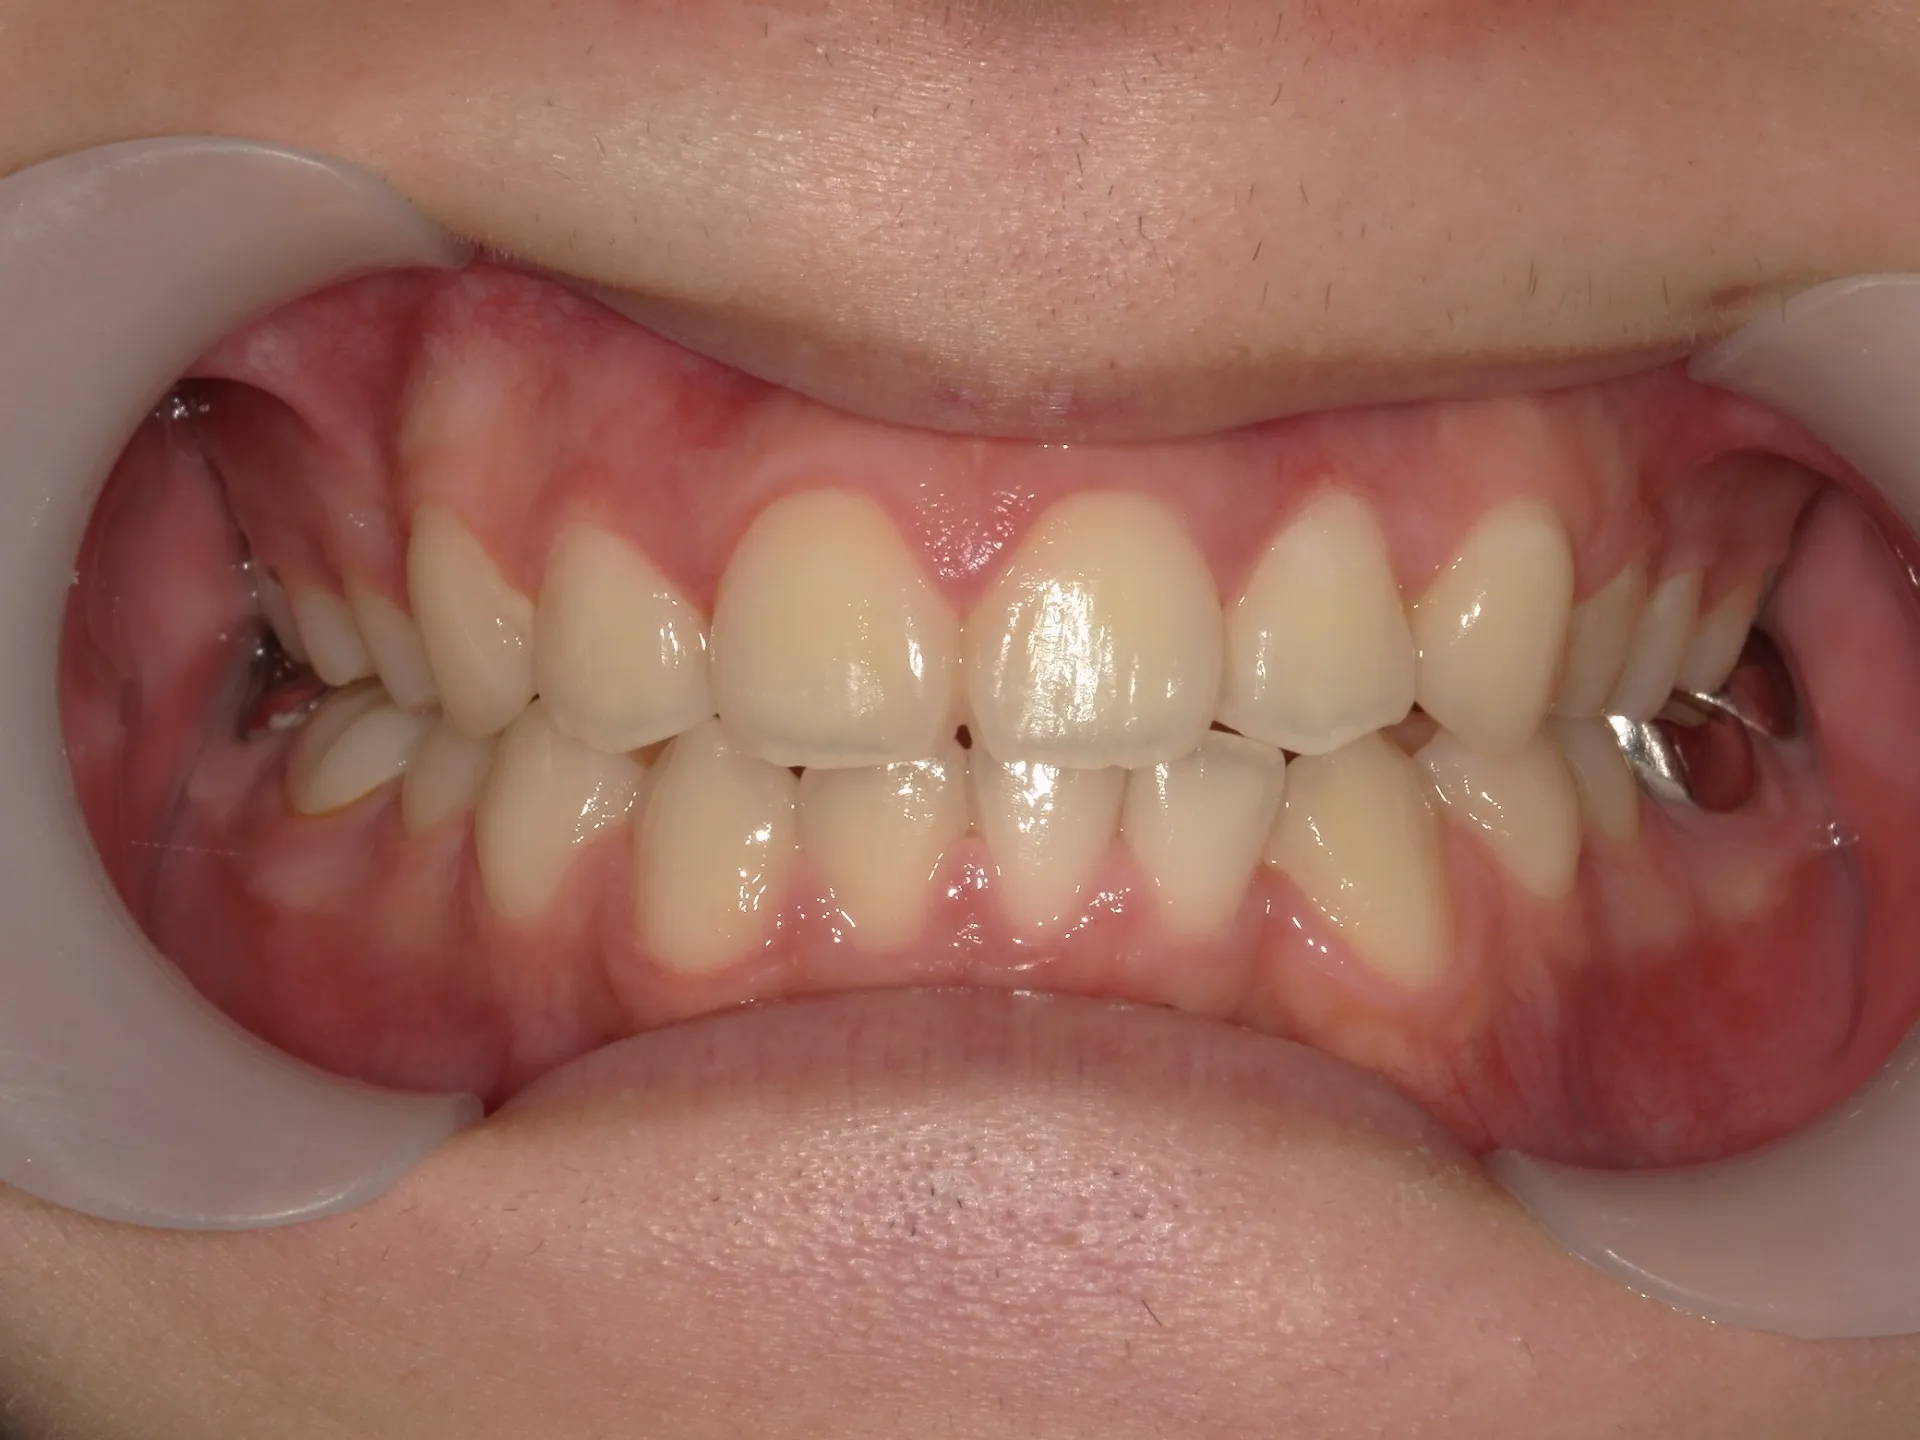

今回は下の前歯が1本ない場合の矯正治療についてご紹介いたします。